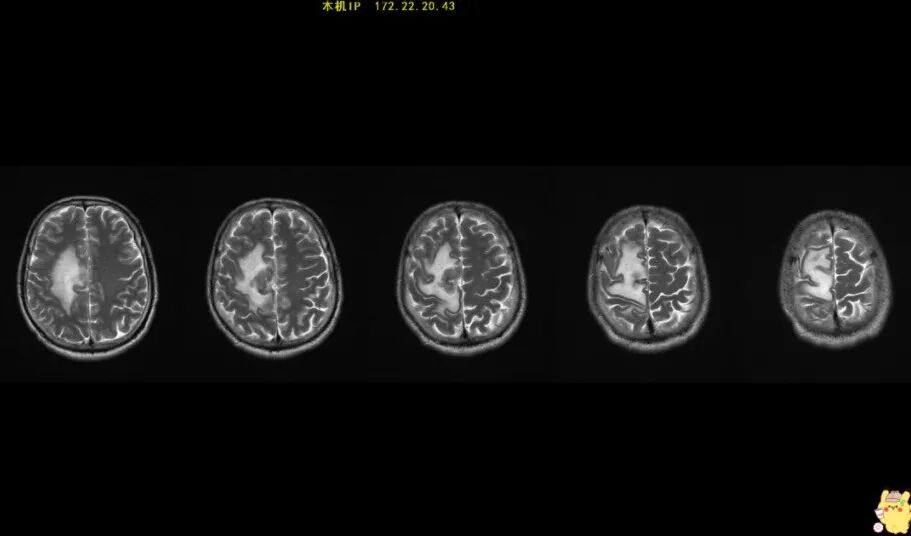

55歲的趙先生(化名)突然癲癇發(fā)作1次,到醫(yī)院做了頭部磁共振,檢查結(jié)果提示是腦腫瘤,考慮膠質(zhì)瘤。醫(yī)生建議他盡快住院進(jìn)行手術(shù)治療。得知要開顱手術(shù),趙先生心生畏懼,考慮癲癇僅發(fā)作一次,也沒(méi)有其他不適,決定回家再觀察一下。然而好景不長(zhǎng),過(guò)了數(shù)月,趙先生回到醫(yī)院復(fù)查,結(jié)果讓他悔恨莫及!此時(shí),腫瘤已經(jīng)明顯增大。趙先生立刻來(lái)到惠州三院神經(jīng)醫(yī)學(xué)中心神經(jīng)外科尋求治療,并順利做了手術(shù)。

趙先生頭部磁共振(箭頭白色區(qū)域處為腫瘤)